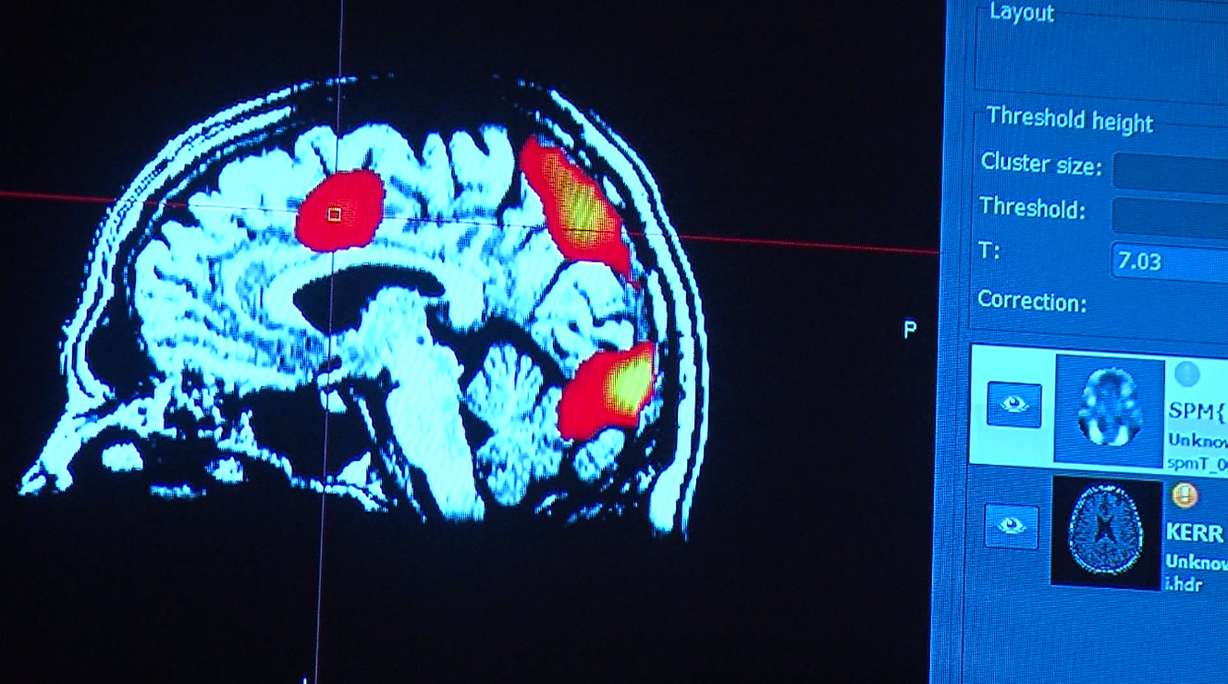

He played last year in the Canadian Football League with the BC Lions. But now he's saying goodbye to pro football and starting a new career. Cognitive FX has developed new methods of using functional MRIs to target therapy on specific damaged regions of the brain.